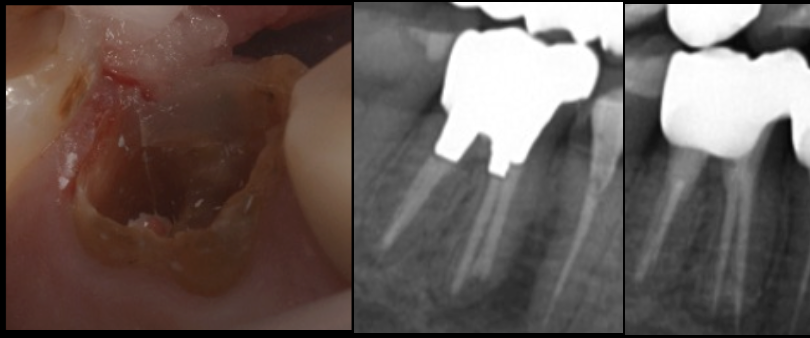

治療前

初診時の口腔内・レントゲンでは、以下の問題点が見られました。

- 二次カリエスによる大きな歯質欠損

- 残根に近いレベルまで崩壊

- 歯質の薄さから保持力がほぼ不可能

- 根尖に透過像(炎症の影)

- 噛むと痛い(咬合性の問題も併発)

- 被せ物が繰り返し脱離している既往

① 精密根管治療

(マイクロスコープ

× ラバーダム)

治療の根幹となるのが、感染源の徹底除去。

ラバーダム防湿+マイクロスコープ拡大視野で、

- 感染した象牙質・根管内の感染物質の除去

- 破折線の有無の確認

- 歯質の厚みと予後の評価

- 根尖部の炎症のコントロール

を丁寧に行います。

特に今回重要だったのは、「破折かどうか」を正確に見極めること。

歯を残せるかどうかは、ここでほぼ決まります。

診断の結果、

致命的な破折はなく、歯質は薄いものの補綴で補強可能と判断しました。

根管治療後には、根尖の透過像が明らかに改善し、炎症もコントロールされました。